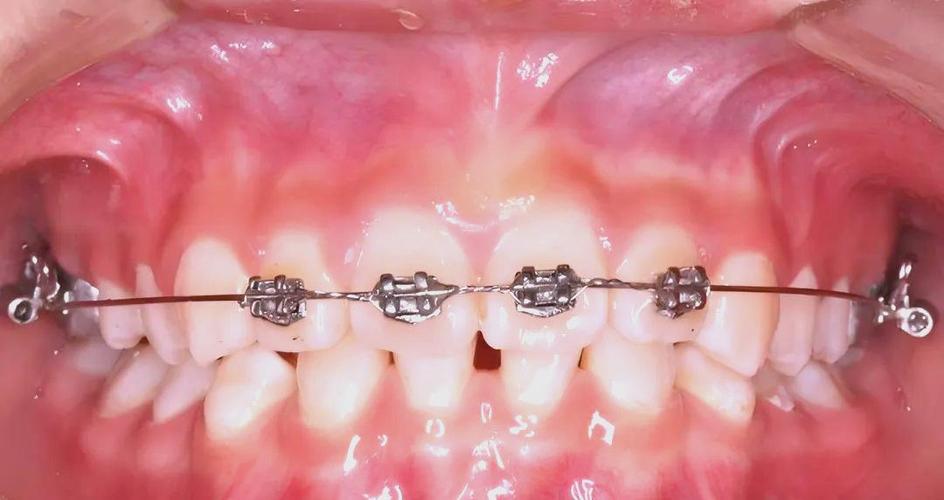

(图片来源网络,侵删)- 定义:仅通过上颌/下颌4颗切牙(2颗中切牙+2颗侧切牙)的托槽,结合磨牙带环进行矫治的固定矫治技术。

粘接托槽

- 上/下颌4颗切牙粘接022英寸标准托槽

- 磨牙粘接带环(含颊面管)